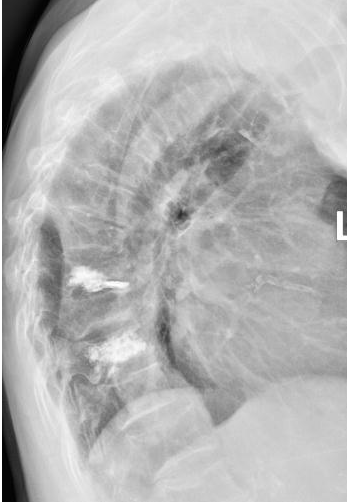

术中,负责人贺毅及团队在C型臂X线透视下,避开神经血管,通过4个3mm的小切口将穿刺针精准抵达骨折部位T9和T11,注入“骨水泥”强化椎体,术中严格控制骨水泥灌注速度与剂量,避免渗漏风险。全程局麻,李奶奶意识清醒,无痛感,出血不足5毫升,术后李奶奶疼痛评分从8分骤降至2分,次日即在支具保护下自主行走,顺利出院。